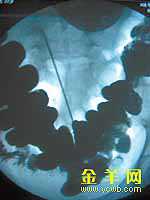

X光片中显示长针插在腹腔中 梁正杰/摄

家住环市西路的阿雄(化名)近两个月来腹痛难耐,9月9日到某医院求医。在诊治中,医生对他进行全身检查时发现其阴部有三个球形肿物,怀疑他有性病,需X光拍片和验血作进一步检查。放射科的医生在拍片时,发现阿雄的腹部有细条状金属异物,建议他再做全消化道X线钡餐透视作细致定位。10日上午,做钡餐显影时,医生通过仪器观察到其腹腔大网膜中确实插有一支针,长约1.43厘米,直径约2毫米,可能已经氧化生锈。医生说,大网膜主要成份是脂肪,由于病人长期吸毒,身体状况较差,大网膜只有薄薄一层,人体若进行剧烈活动,针有可能刺穿腹部的大动脉,引起大出血。